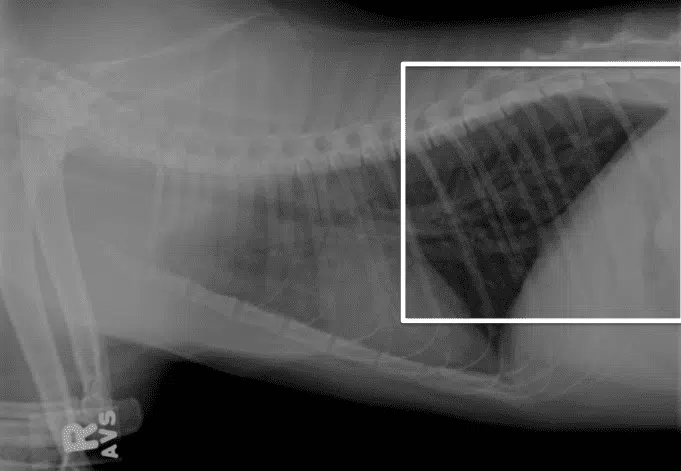

8) Una respuesta correcta

- Efusión pleural (se ven los lobulos pulmonares dibujados por liquido fuera del pulmon)